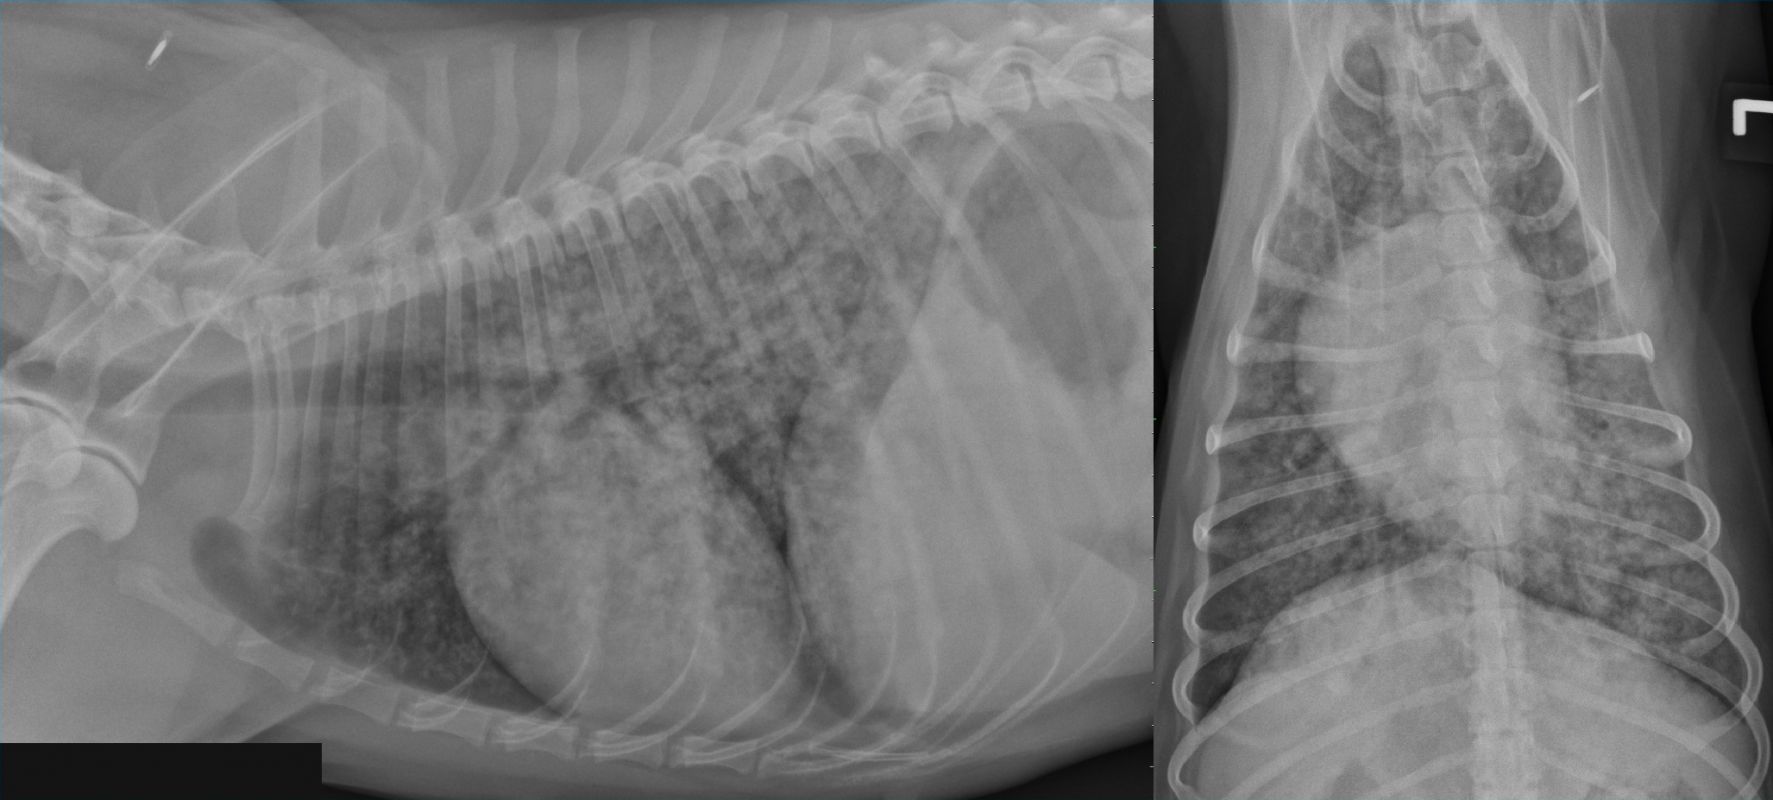

From 2010vets.blogspot.com

Veterinary, Photography and Travel Stories for vet students and pet Lung Issues In Older Dogs If your old dog’s breathing gradually gets worse and worse, don’t assume it’s okay, and don’t assume nothing can be done. — older dog breathing heavily—with older dogs, underlying medical conditions are more likely such as heart. — dyspnea, or troubled breathing, and tachypnea, or rapid breathing, panting or coughing can all be signs of serious underlying. However,. Lung Issues In Older Dogs.